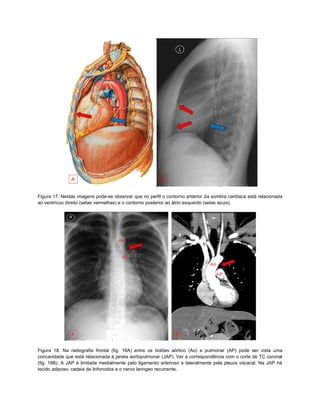

Figura 17. Nestas imagens pode-se observar que no perfil o contorno anterior da sombra cardíaca está relacionada

ao ventrícuo direito (setas vermelhas) e o contorno posterior ao átrio esquerdo (setas azuis).

Figura 17. Nestasimagens pode-se observar que no perfil o contorno anterior da sombra cardíaca está relacionada ao ventrícuo direito (setas vermelhas) e o contorno posterior ao átrio esquerdo (setas azuis). Figura 18. Na radiografia frontal (fig. 18A) entre os botões aórtico (Ao) e pulmonar (AP) pode ser vista uma concavidade que está relacionada à janela aortopulmonar (JAP). Ver a correspondência com o corte de TC coronal (fig. 18B). A JAP é limitada medialmente pelo ligamento arterioso e lateralmente pela pleura visceral. Na JAP há tecido adiposo, cadeia de linfonodos e o nervo laringeo recurrente.